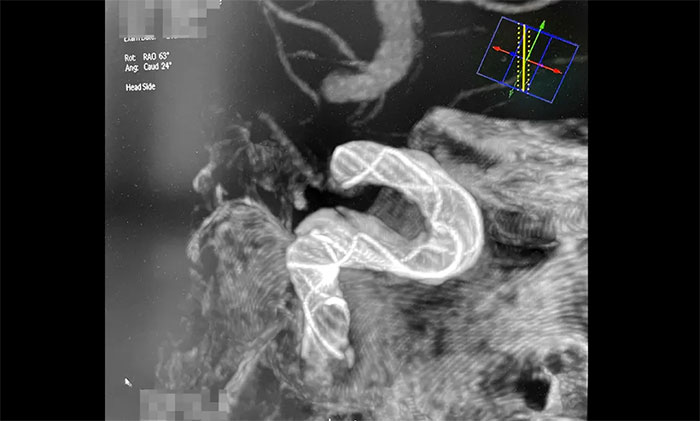

術中,席剛明教授、王貴平博士克服血管迂曲困難,經(jīng)過多次嘗試,多次球囊擴張、“按摩”后,最終順利釋放密網(wǎng)支架至左頸內動脈眼動脈段、左頸內動脈床突段、左頸內動脈海綿竇段。造影及3D造影見,動脈瘤瘤內造影劑明顯滯留,左頸內動脈、左大腦前動脈顯影可,載瘤動脈通暢,獲得了理想的血管重建。復查造影,左頸總動脈造影見左頸總動脈、左頸內動脈、左大腦前動脈顯影可。CT見支架打開貼壁滿意,XperCT未見顱內出血,手術圓滿完成,順利拆除“不定時炸彈”并打通大腦生命線。

▲ 順利拆除“不定時炸彈”